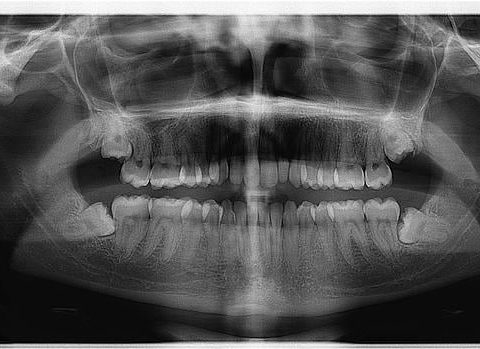

Causas

La acumulación de sarro provoca la aparición de bacterias que irritan las encías hasta provocar focos de infección que se van llenando de toxinas y bacterias. A medida que la enfermedad avanza sin que le pongamos remedio, la infección penetra hasta el hueso que sostiene los dientes hasta dañarlo y/o destruirlo.